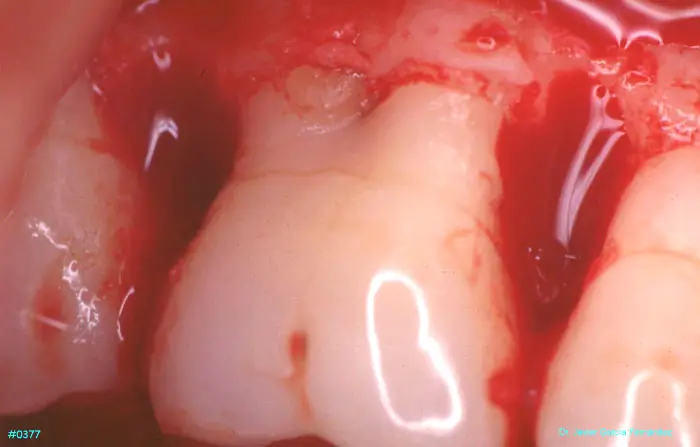

ATLAS DE CIRUGIA PERIODONTAL

imagen 428